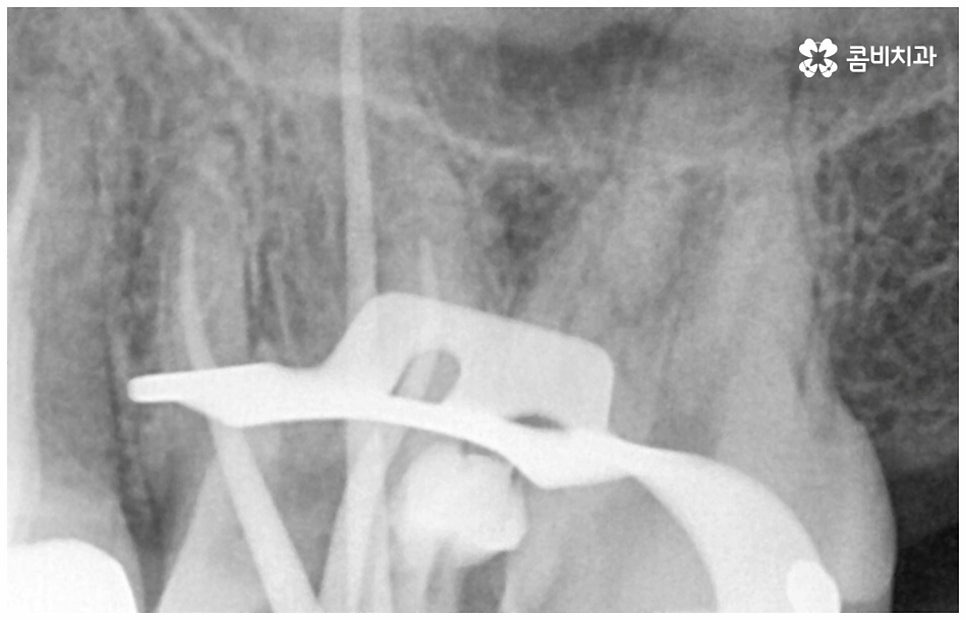

또한 어금니 신경치료를 할 때 러버댐 장착은 필수적인데요 (사진에서 볼 수 있는 하얀막), 이와 같이 고무막으로 치료할 치아만 빼고 나머지는 격리시키는 이유는 해당 부위로 침이 유입되는 것을 막고 최대한 습기를 예방하여 (방습법) 치료의 효율성과 치과 재료 기능을 향상시키는 것, 환자와 시술자간 교차 감염을 막아 오염 확률을 낮추는 것, 신경 치료할 때 쓰이는 약제 또는 치아 삭제시 생기는 찌꺼기 등이 입 안으로 흘러 들어가는 현상을 방지하는 것 등등 환자분들을 보호하고 치료의 질을 높이기 위한 목적이니 안쪽 치아라서 조금 불편하시더라도 필요성에 대해서 잘 인지하시길 바라고 있어요.

감염 조직을 완전히 제거하지 않으면 통증이 지속될 수 있고 재발 가능성 또한 높아지므로 어금니신경치료 시 담당의 선생님의 높은 숙련도 및 세심한 기술력이 요구되고 있는데요. 혹시 모를 부작용을 방지하기 위해 3D CT 와 같은 정밀 진단 기계를 갖추고 신경관의 위치와 모양, 환자분들의 골조직 및 치아까지의 거리 등을 꼼꼼하게 파악하여 치료 계획을 세운 후 손상 부위를 세심하게 제거한다면 고난도의 경우라도 보다 안전하게 진행할 수 있어요.